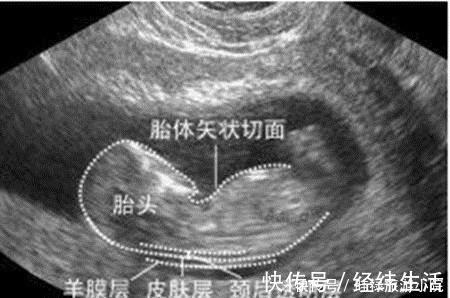

检查时间:怀孕早期到怀孕中期,一般在孕12周产检时检查。这项检查大概在孕11周6天时开始检查,又称为“胎儿颈透明膜厚度的检查”,这项检查对检查时间有严格要求,因而孕妈要提前预约好,按时去做检查。检查方法:通过B超来测量胎儿颈部后方透明膜的厚度,来初步判断胎儿神经管发育的情况,是否存在畸形。如果透明膜过厚,就可能提示:胎儿存在神经管发育的畸形。

京妈建议:① 由于NT检查是最早的关于胎儿智力方面的筛查,因此孕妈一定要严格把控时间做好孕检,及时了解胎儿发育的情况;② NT检查是通过B超来进行的,而且可能是在第一次正规产检时做,不少孕妈会紧张,不过还是建议孕妈尽量避免紧张焦虑,积极配合好医生的检查;③ 如果检查的结果显示:胎儿颈透明膜厚度过厚,孕妈要及时和医生沟通,听从医生的意见。